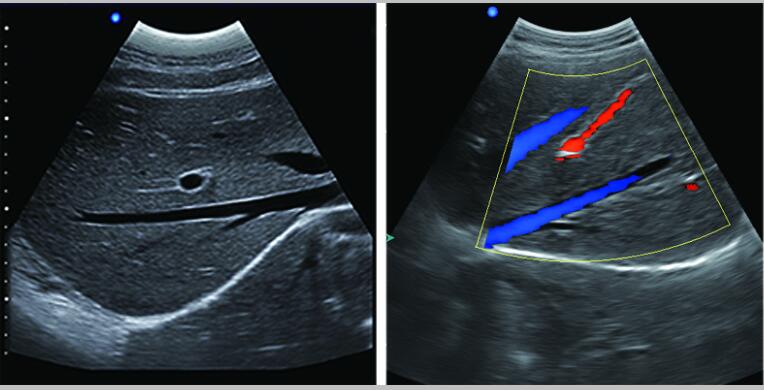

7.應(yīng)用:腹部、婦科、產(chǎn)科、心臟、血管和小器官、泌尿科、肌肉骨骼、兒科等